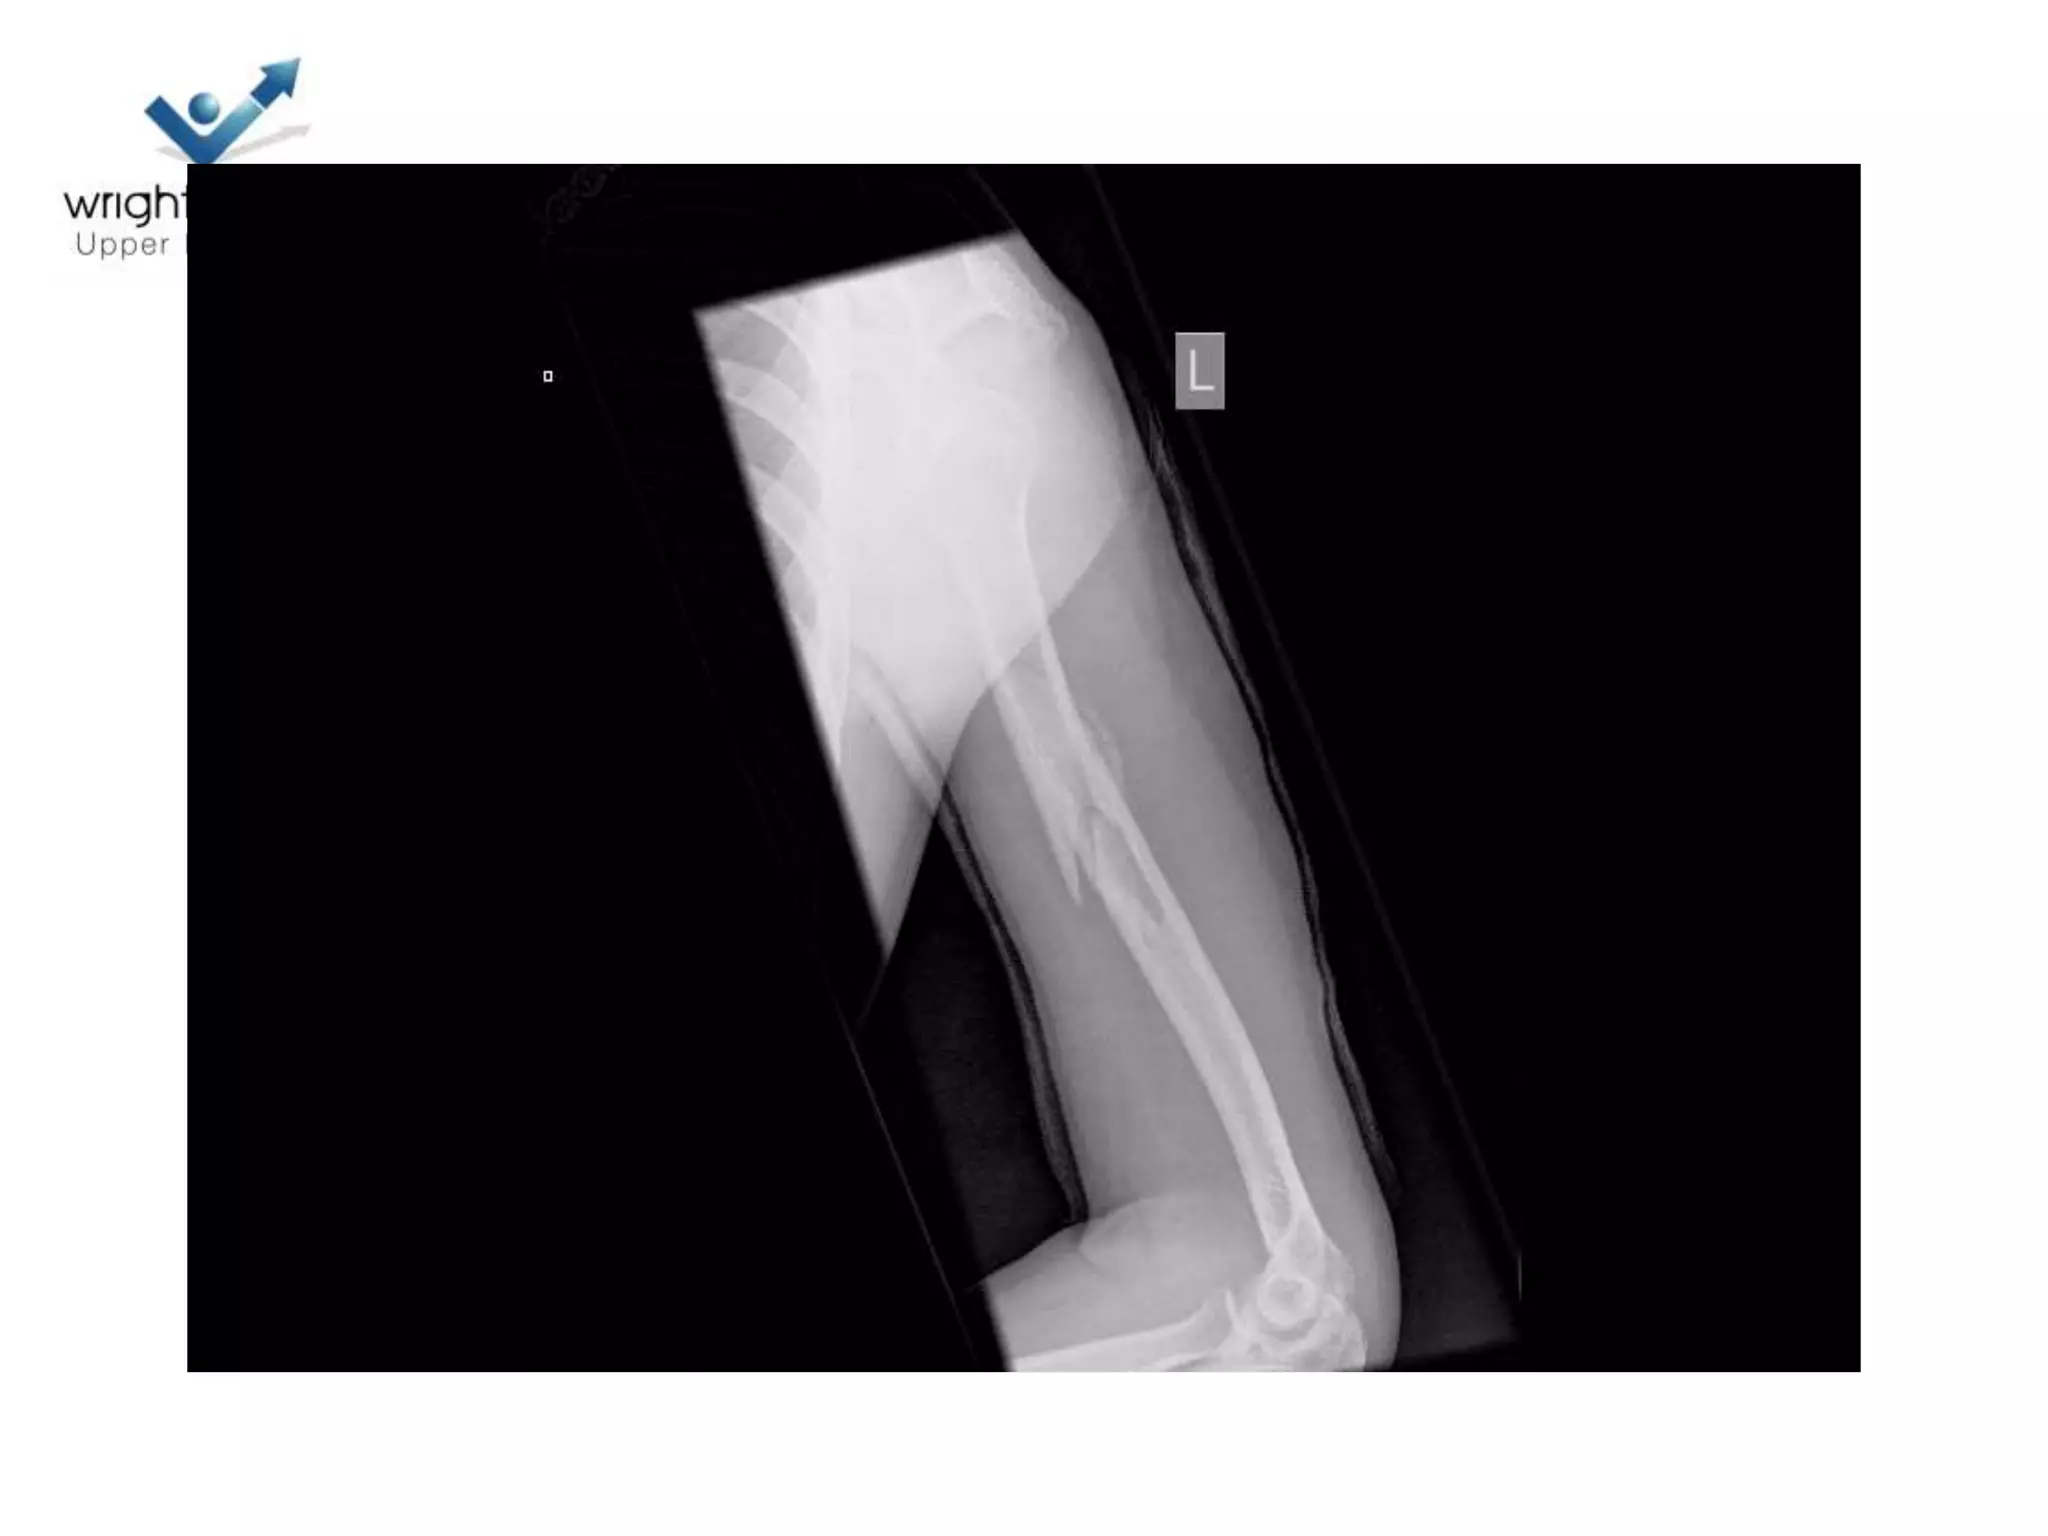

17 Polytrauma

Indications to operate

• Prevent Non union

– Shaft pulled medially

• # dislocations

– If associated with neck

fractures